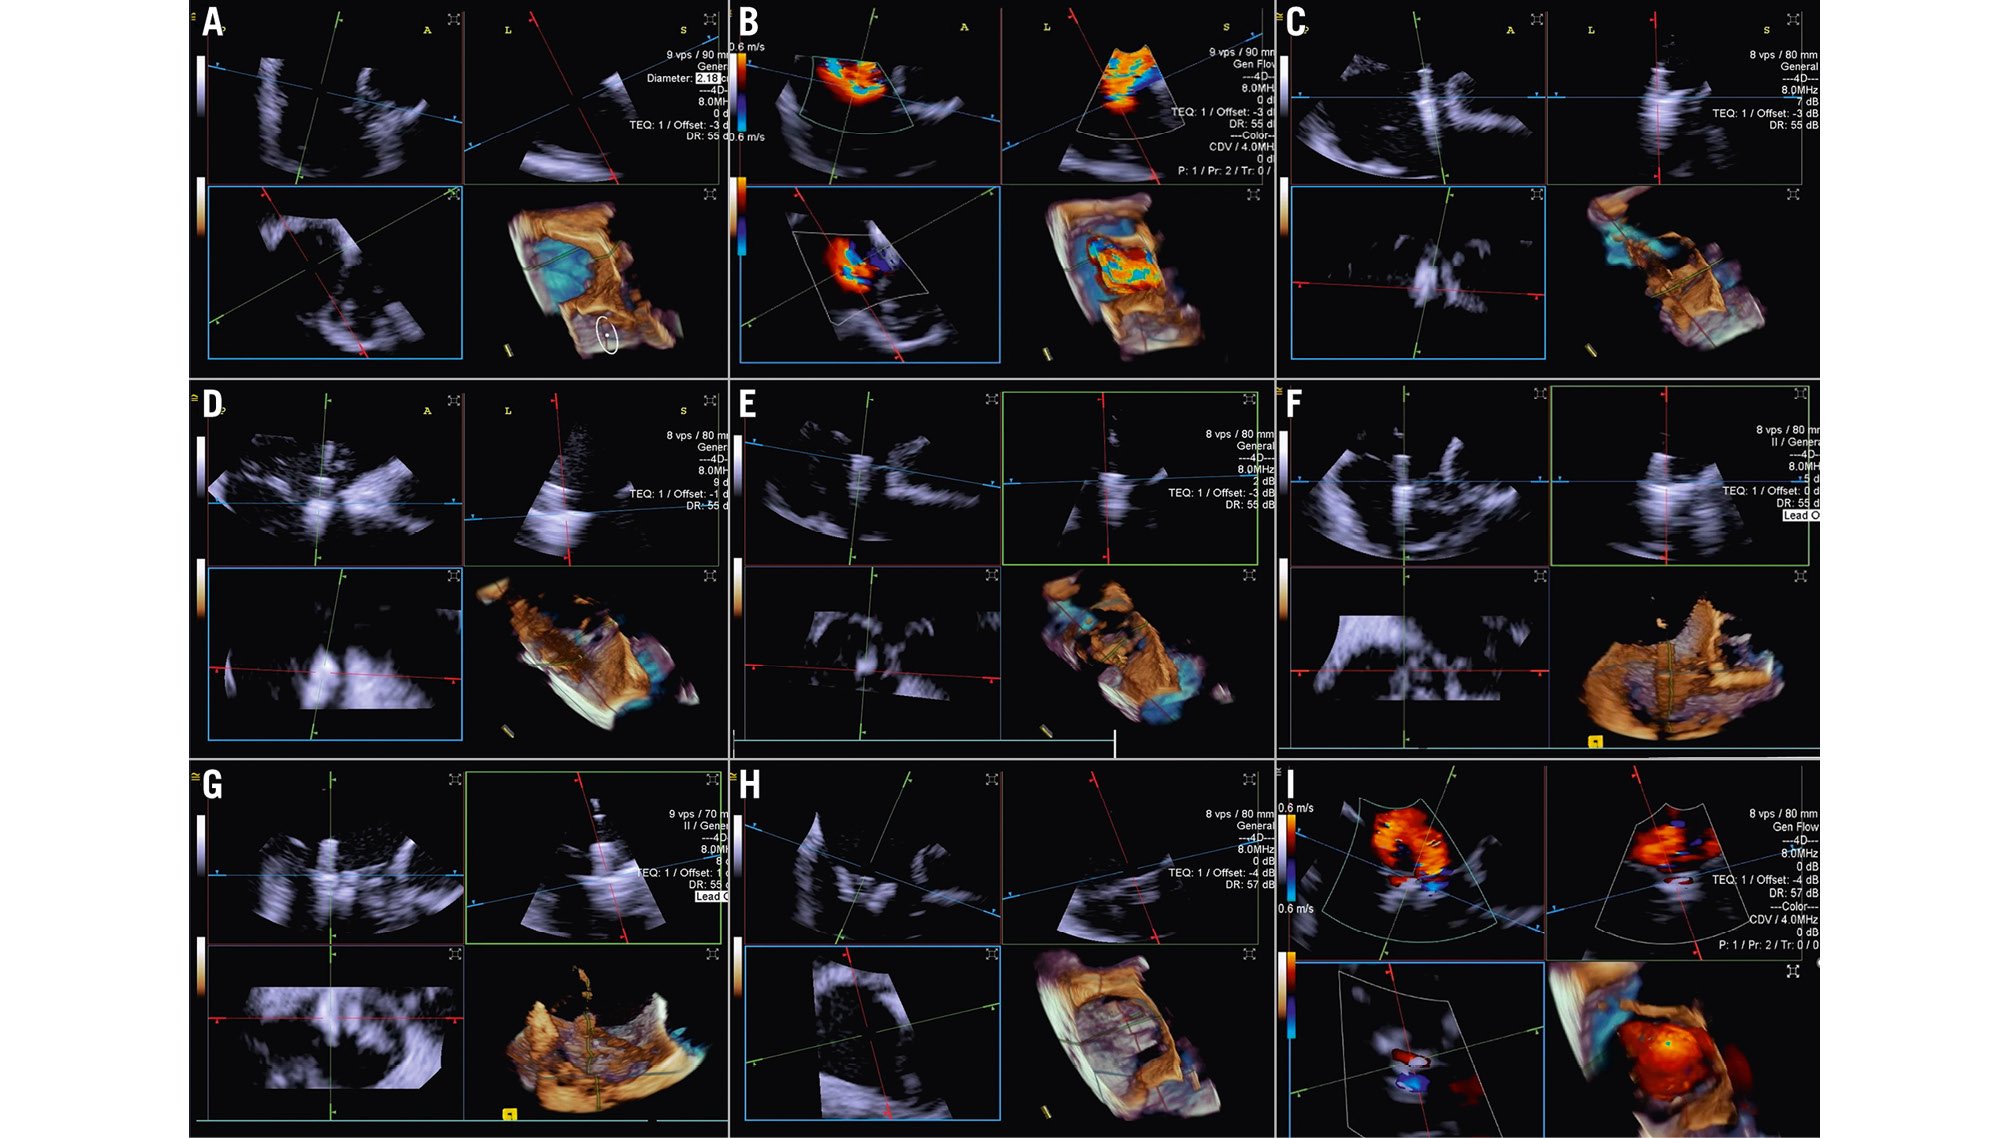

When performing a tricuspid TEER procedure (TriClip [Abbott], PASCAL [Edwards Lifesciences]), shadowing from mitral/aortic prostheses, septal hypertrophy, and other factors are particularly problematic when assessing for leaflet insertion. Three-dimensional ICE is a useful alternative for leaflet insertion in edge-to-edge repair. Starting from the home view (right ventricular inflow view), the use of biplane imaging creates a potential grasp view. Subsequently, a live 3D volume image can be obtained and used for a live 3D MPR16. Similar to TOE, 3D ICE also can be used for trajectory and alignment (Figure 4, Moving image 2-Moving image 3-Moving image 4-Moving image 5-Moving image 6-Moving image 7).

Figure 4. Three-dimensional ICE-guided tricuspid transcatheter edge-to-edge repair. A) 3D MPR ICE imaging planes with posterior and anterior leaflets in the TV home view (top left), septal leaflet and anterior/lateral grasping view (top right). The blue plane (bottom left) represents the short-axis (atrial en face) view of the TV leaflets. Finally, the corresponding 3D volume (bottom right; the aorta is at 5 o’clock). B) 3D colour MPR ICE imaging shows severe tricuspid regurgitation, allowing assessment of the number of regurgitation jets and jet location. C-E) The first device is advanced under the tricuspid valve. Clip orientation is optimised to be orthogonal to the coaptation line while the clip position is fine-tuned to the target location, and independent leaflet grasping is performed. F) 3D MPR assessment of second device orientation and location. G) 3D MPR assessment of third device orientation and location. H, I) 3D MPR and colour-flow Doppler final assessment of the devices. 3D: three-dimensional; ICE: intracardiac echocardiography; MPR: multiplanar reconstruction; TV: tricuspid valve

Moving image 2. 3D RT MPR ICE imaging planes with the TV home view (top left), septo-lateral grasping view (top right), short axis (atrial en face) view of TV leaflets (bottom left) and the corresponding 3D volume (bottom right) with the aorta at 5 o’clock.

Moving image 3. 3D RT MPR ICE showing severe tricuspid regurgitation.

Moving image 4. 3D RT MPR views of independent leaflet grasping.

Moving image 5. 3D RT MPR views showing T-TEER device after grasping.

Moving image 6. 3D RT MPR assessment of stability after deployment of three T-TEER devices.

Moving image 7. 3D colour RT MPR result following T-TEER.